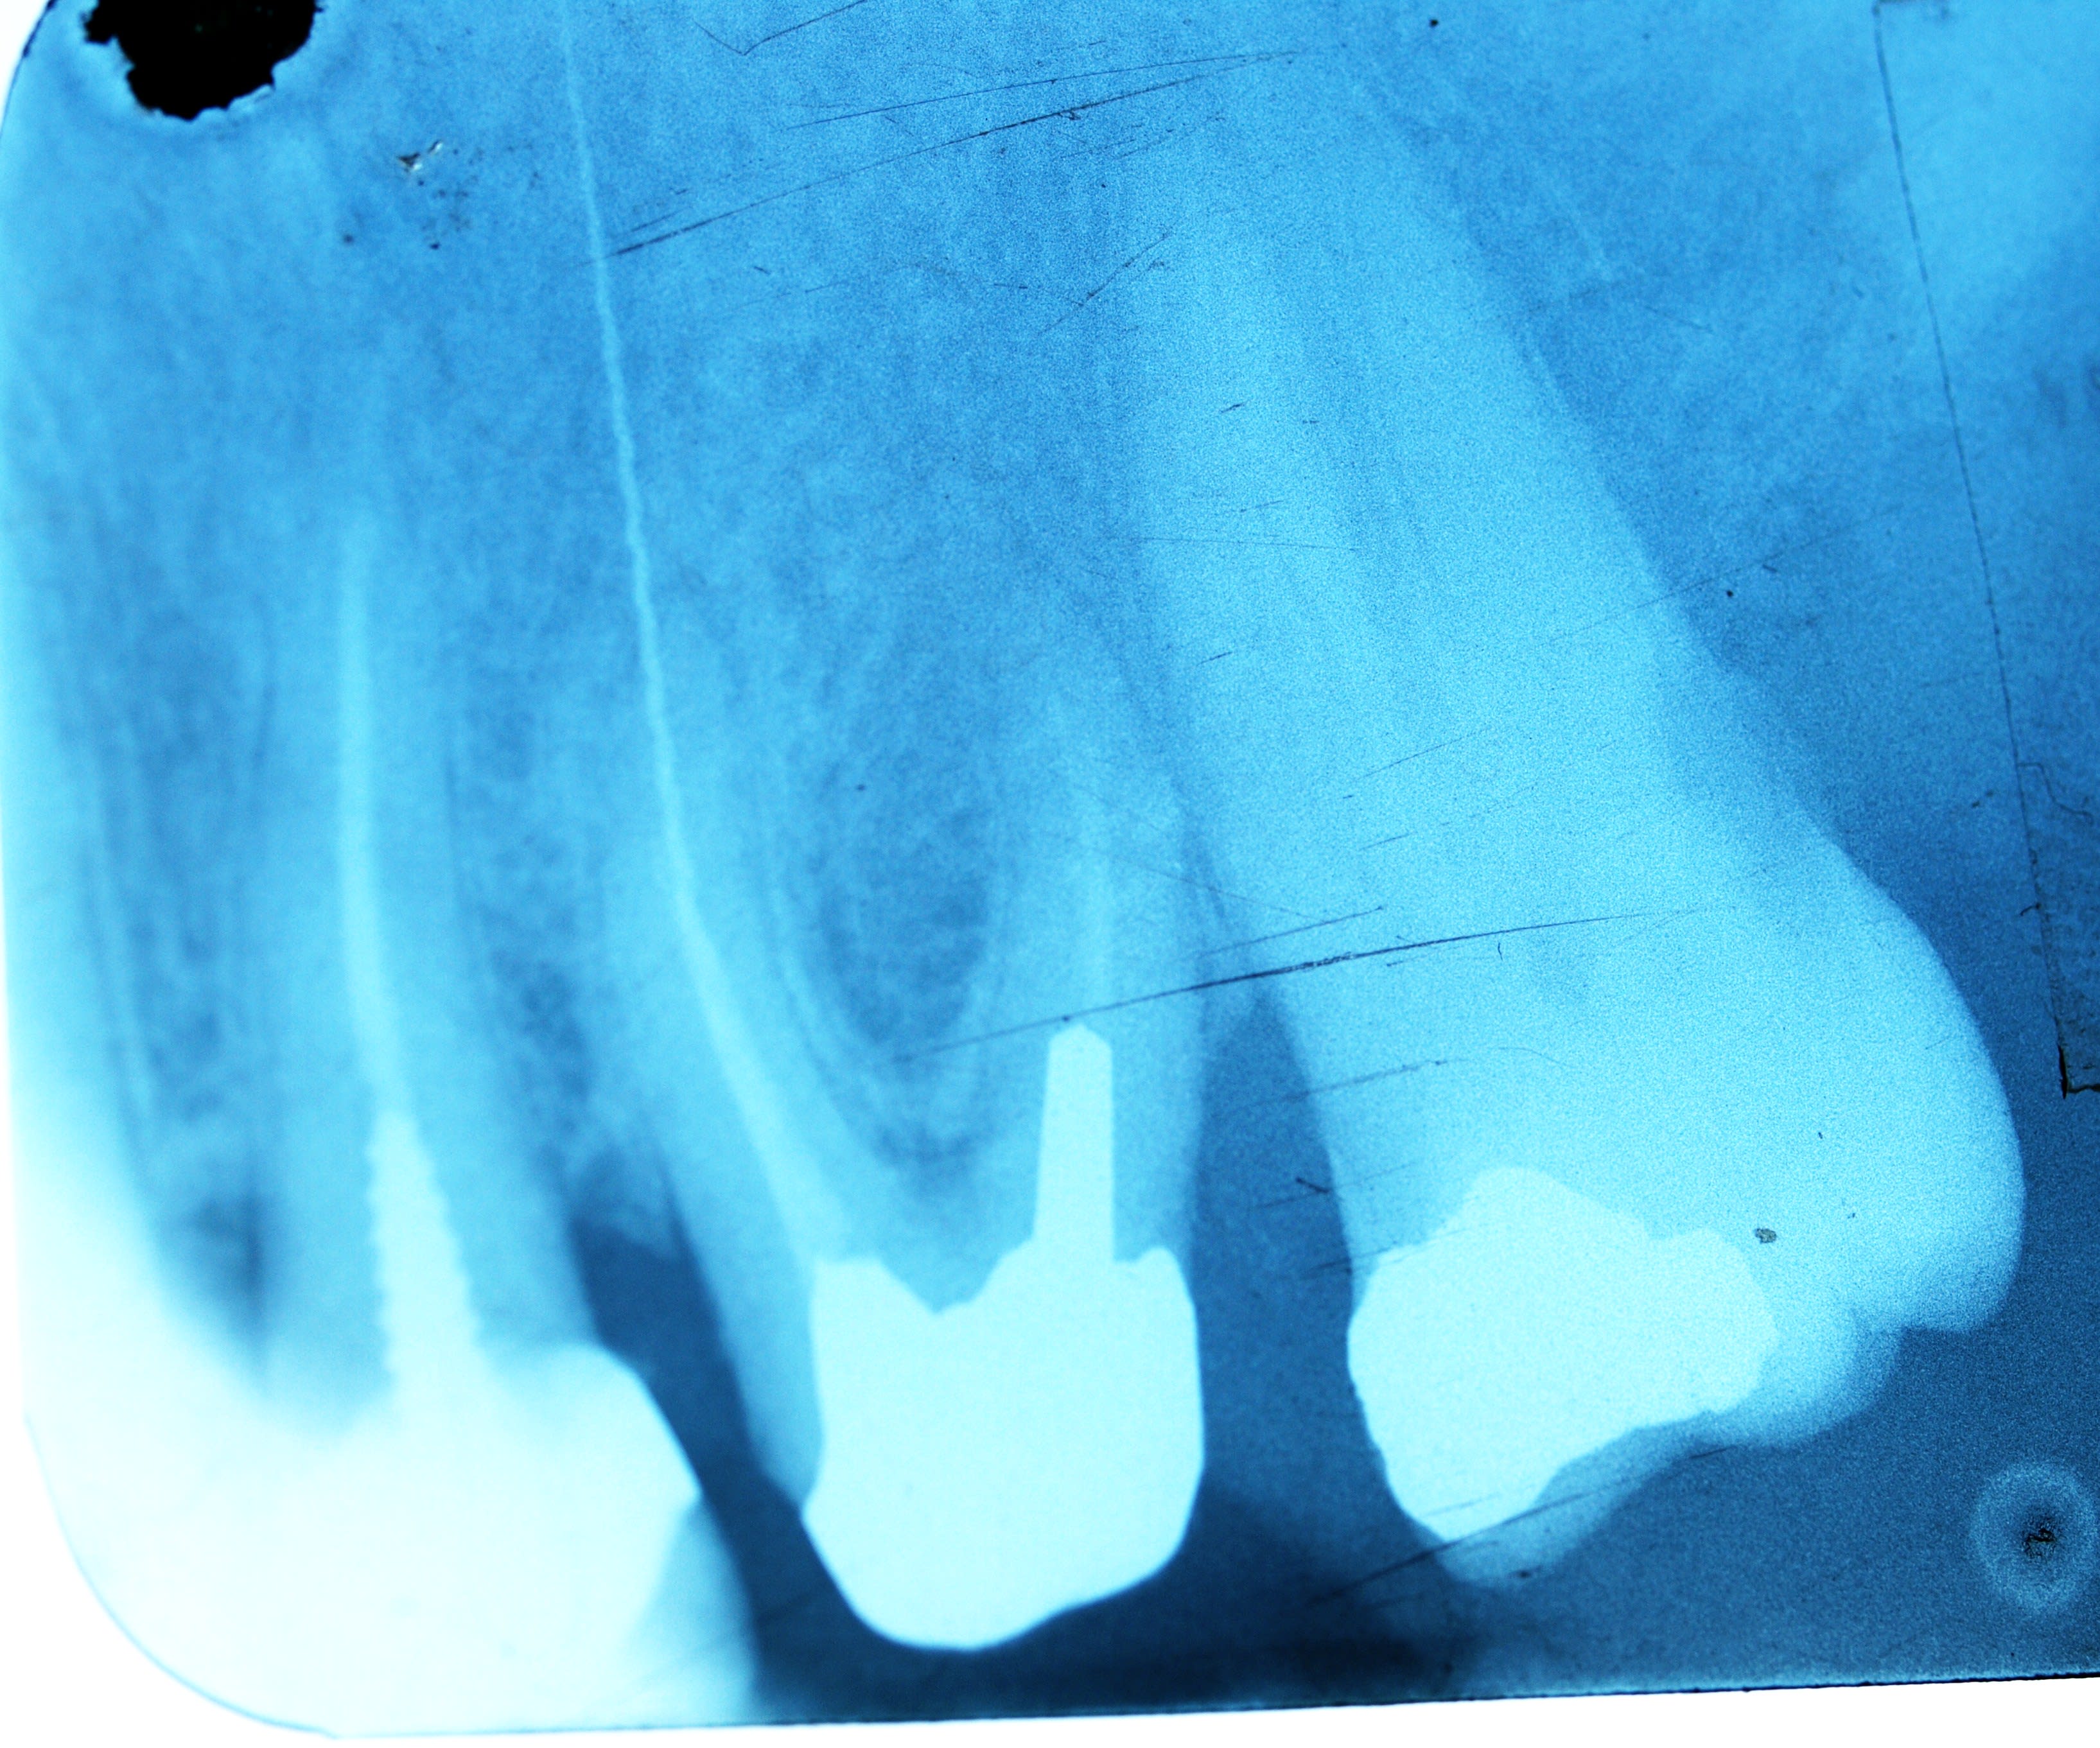

Aujourd'hui je suis tombé sur une ancienne contre angle d'endo Micromega 6AE15 que j'ai achetée il y a plusieurs années et dont je ne sais pas son utilité. Lorsque je l'ai fait marché j'ai remarqué qu'elle fait un mouvement de réciprocité 50%à droite et 50% à gauche.

Aujourd'hui j'ai décidé d'utiliser mon gyro bien que je dispose d'un moteur endo avec localisateur d'apex intégré.ça à marché à merveille avec les limes CMA en attendant de trouver les gyrofiles. ..je me suis dit pourquoi pas avec les autres limes de rotation continue ...vraiment c'était top.